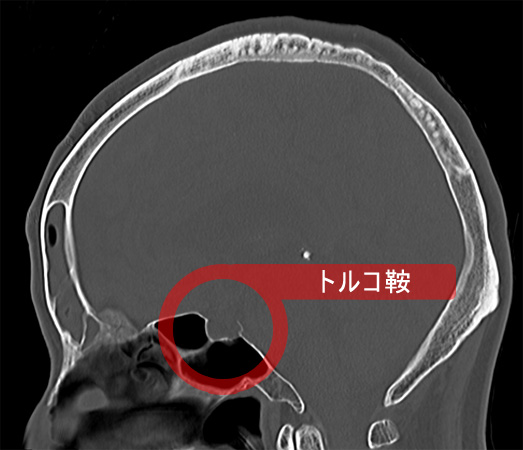

下垂体は鼻の付け根の奥のトルコ鞍という頭蓋骨の小さなポケット(大きさ1cm大)のようなところにあります。

トルコ鞍の中で成長し、大きくなるとトルコ鞍から頭蓋内へ突出し(鞍上部へ突出し)、脳神経を圧迫します。腫瘍が鞍上部へ突出し視神経を強く圧迫すると、視機能の低下(視野欠損、視力低下)を招きます。視野欠損は両耳側半盲といって、両目の外側(左右の目の耳側)の視力が欠けてしまいます。この状態になると、人混みでぶつかり易くなったり、車の運転で衝突事故を起こしやすくなります。